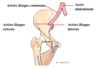

Identifiez